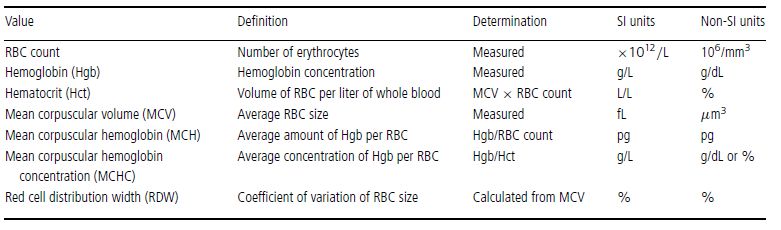

Erythrocyte morphology, number, size, and hemoglobin content are evaluated by peripheral blood smear examination and also through a combination of measurements and calculations, usually with the aid of automated instruments. These erythrocyte values include RBC count, hemoglobin (Hgb), hematocrit (Hct), mean corpuscular volume (MCV), mean corpuscular hemoglobin (MCH), mean corpuscular hemoglobin concentration (MCHC), red cell distribution width (RDW), reticulocyte count, and reticulocyte production index (RPI) (in dogs only). The RBC count, Hgb, and MCV are measured, whereas the Hct, MCH, MCHC, and RDW are calculated (Table 1.2). The RPI is calculated using the reticulocyte count, which is usually determined manually.

Table 1.2 Erythrocyte values used in the complete blood count (CBC)